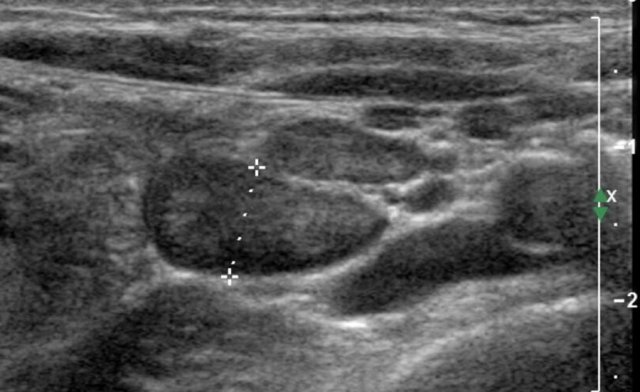

Mesenteric lymph nodes

Adapted from reference 15 Adapted from reference 15

Materials and method

In this retrospective study in 61 children (36 boys and 25 girls, mean age 10.7 years, range 1.1-17.3 years) who underwent non-contrast abdominal CT examination for evaluation of suspected or known renal stones abdominal lymph node size was evaluated.

It is assumed that these CT findings can be extrapolated to ultrasonography.

Enlarged mesenteric lymph nodes (short axis > 5 mm) were found in 33 (54%) of the 61 children.

The majority of the enlarged mesenteric lymph nodes were found in the right lower quadrant (88%).

Based on their findings the authors state that: using a short-axis diameter of >8 mm might be a more appropriate definition for mesenteric lymphadenopathy in children.